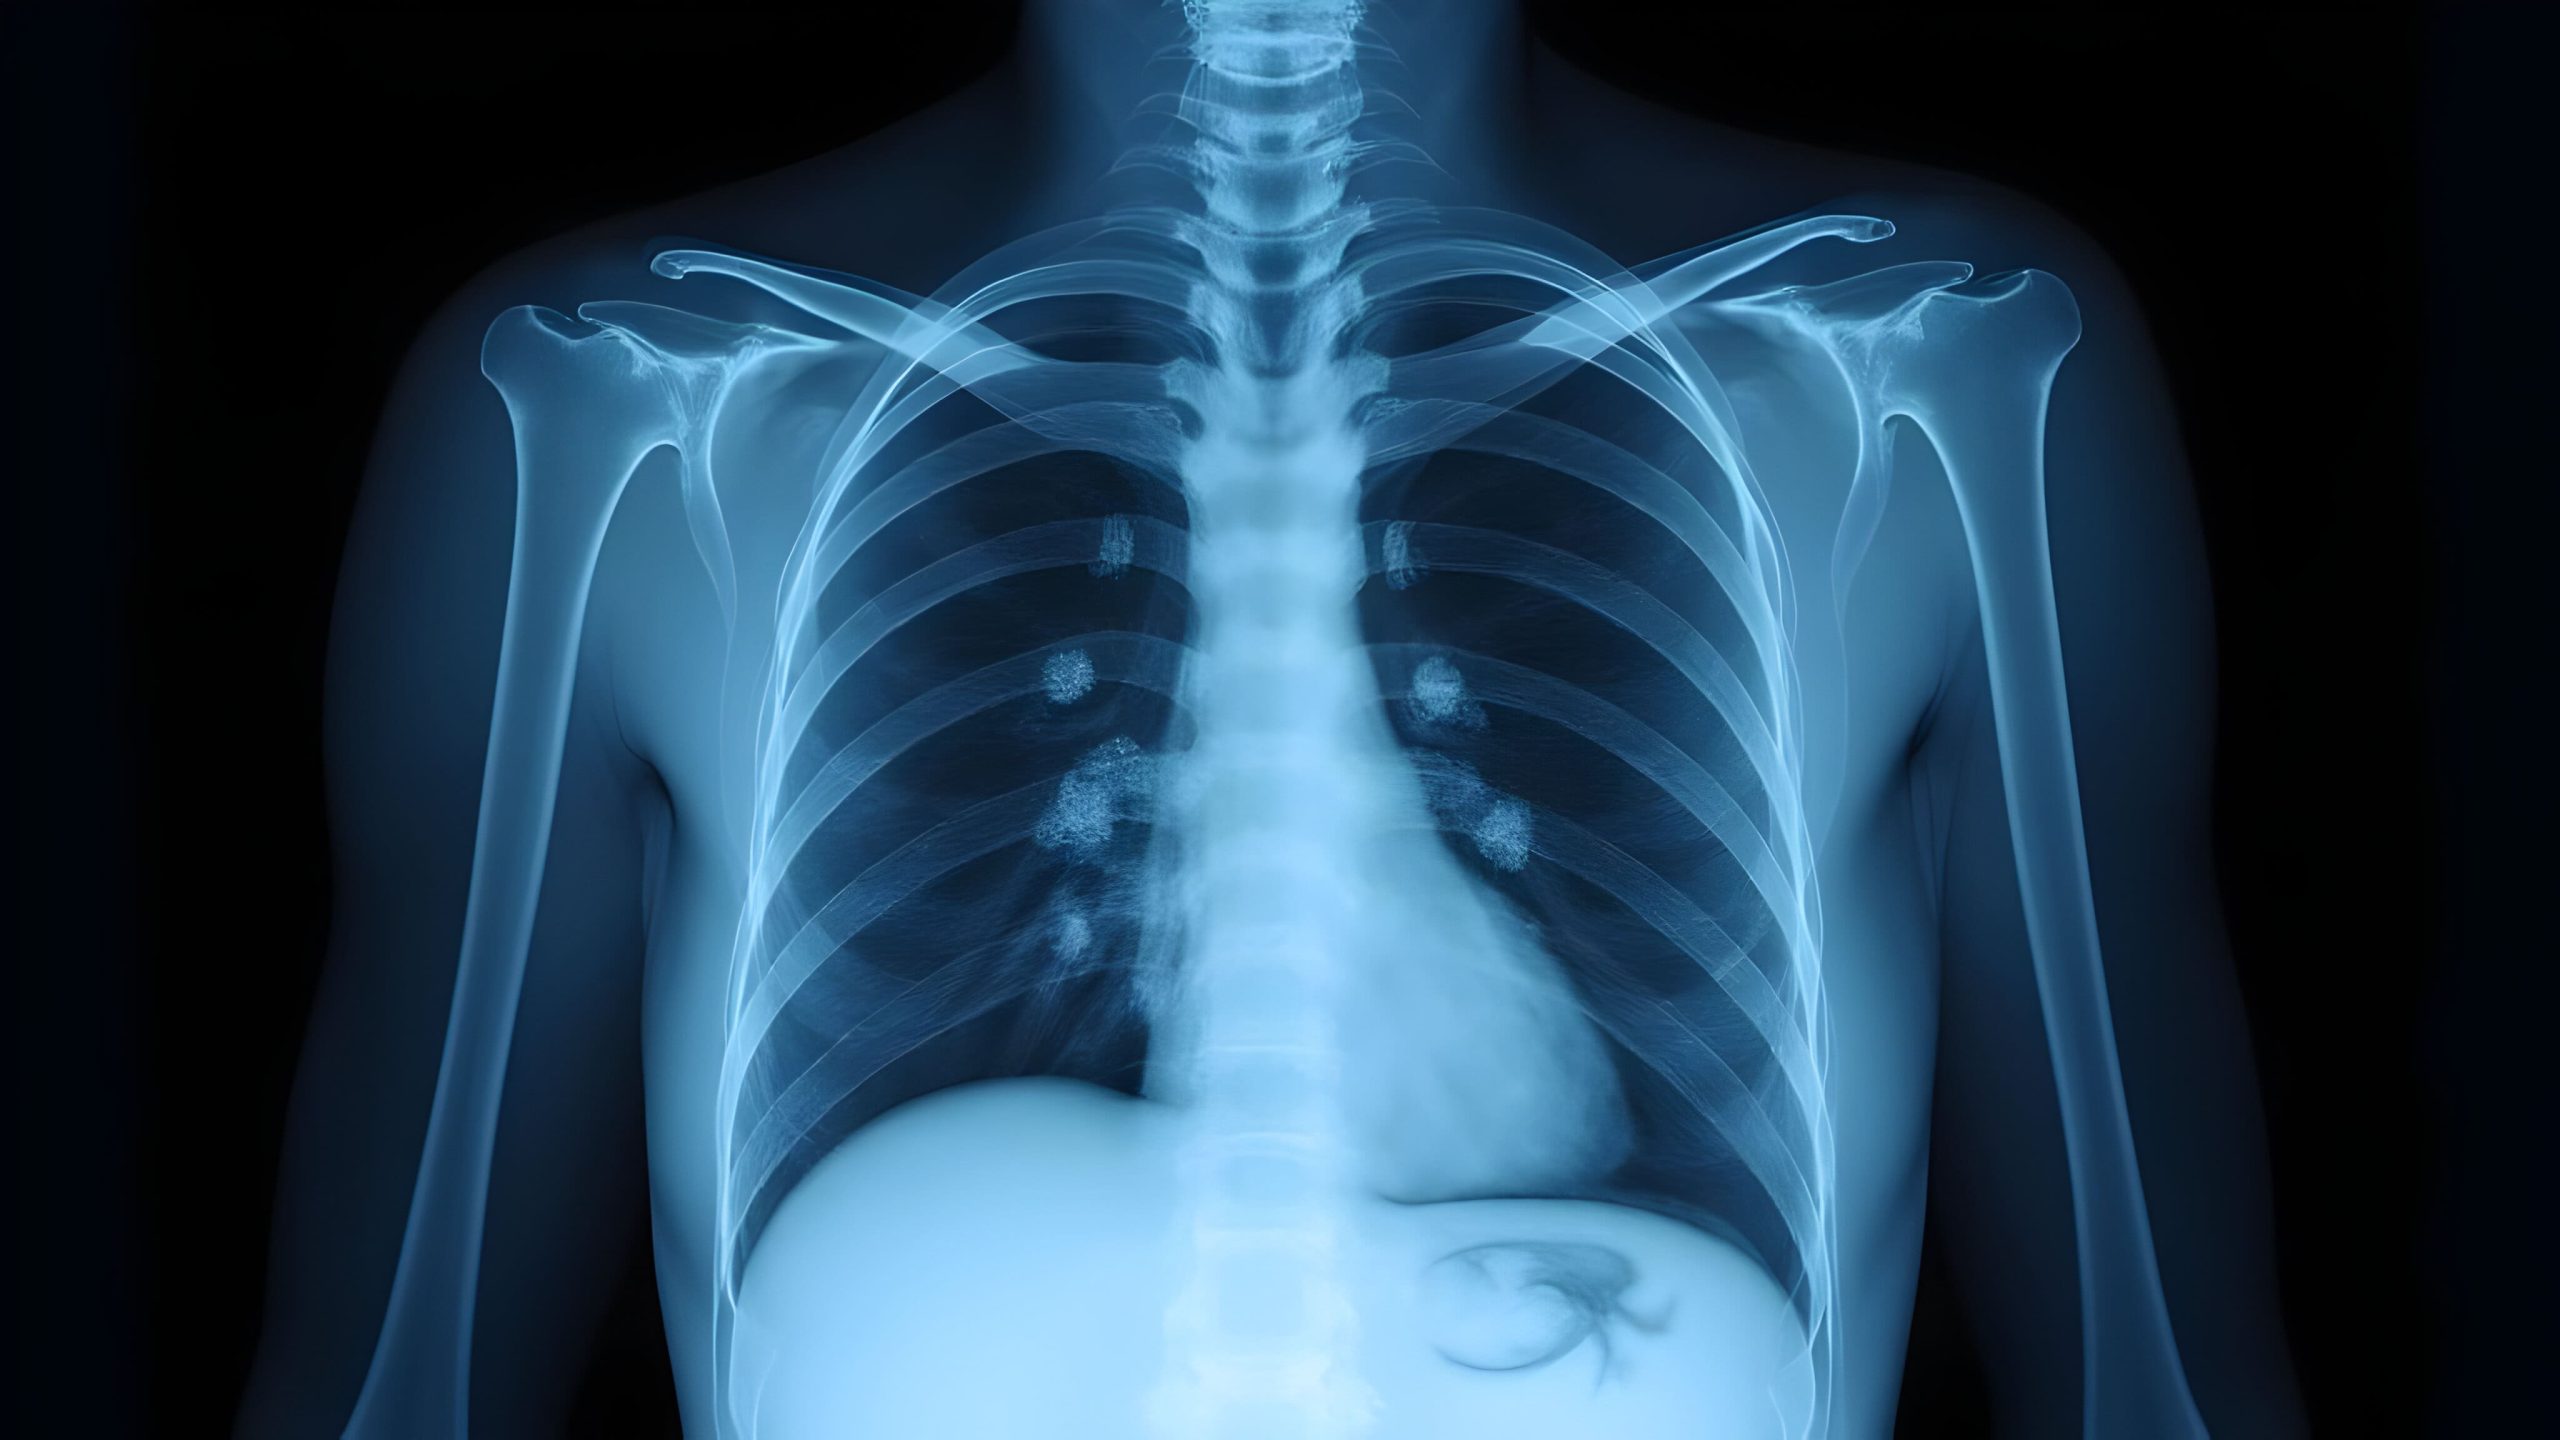

Raio-X de tórax

É frequentemente o primeiro exame solicitado. Pode mostrar áreas de opacidade no pulmão ou alterações no contorno torácico, mas nem sempre consegue detectar derrames pequenos (menores que 200 mL).